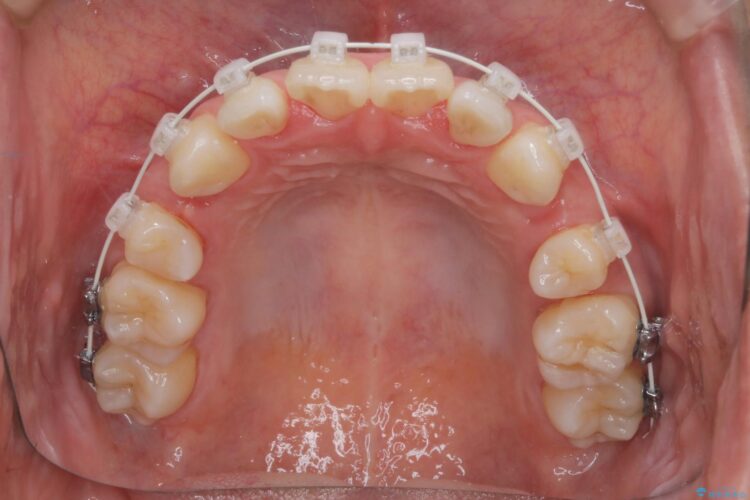

重度の叢生が認められたため、上下左右4番目の歯を抜歯しワイヤー矯正治療を行いました。

前歯のデコボコが改善され、噛みあわせも綺麗になりました。

歯肉退縮もなく、予定通りに治療を終えることができ大変ご満足いただけました。